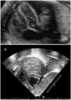

A pericardial effusion is an abnormal accumulation of fluid in the pericardial cavity. The pericardium is a 2-part membrane surrounding the heart: the outer fibrous connective membrane and an inner 2-layered serous membrane. [Source: Wikipedia ]